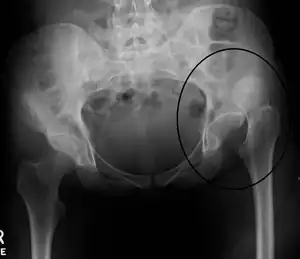

| X-ray showing a joint dislocation of the left hip. | |

Anterior-posterior (AP) X-rays of the pelvis, AP and lateral views of the femur (knee included) are ordered for diagnosis.[13] The size of the head of the femur is then compared across both sides of the pelvis. The affected femoral head will appear larger if the dislocation is anterior, and smaller if posterior.[14] A CT scan may also be ordered to clarify the fracture pattern.